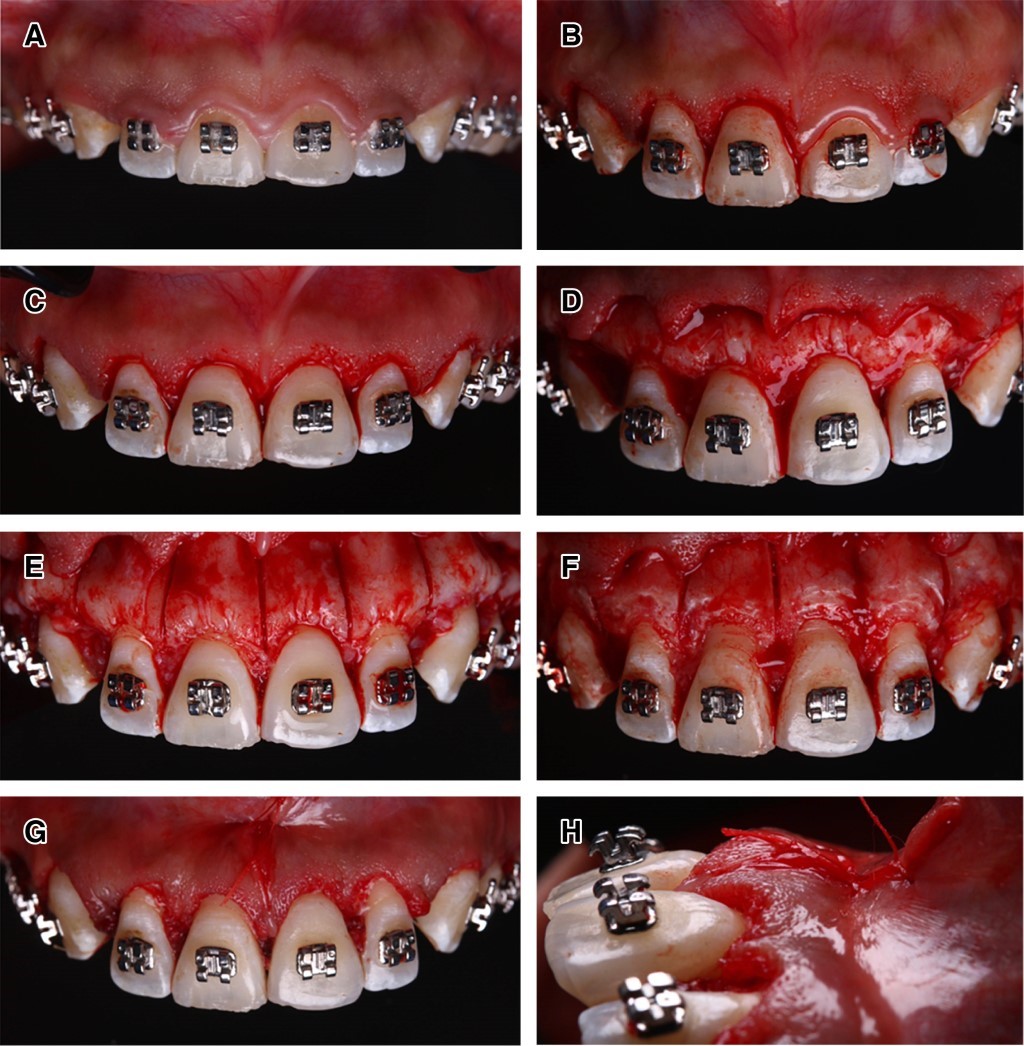

Bajo anestesia local en la arcada superior, se realizó la remoción de tejido de inserción supracrestal de órganos dentarios 1.5 a 2.5, posteriormente se realizaron incisiones sulculares y se elevó colgajo de espesor total para exponer la cortical ósea vestibular. Con el piezoeléctrico, se realizaron corticotomías en sentido vertical en el área interradicular, del largo de la raíz. Posteriormente, se eliminaron exostosis y se realizó recontorneo gingival, así como la desinserción del frenillo labial. Se suturó con puntos en 8 por palatino con Vicryl 5-0. Se retiraron puntos a los siete días (Figura 3).

Se realizó seguimiento tres meses posteriores donde se observa el antes y después en la cicatrización de los tejidos periodontales y el avance satisfactorio del tratamiento ortodóncico (Figura 4).

Figura 3

Figura 4